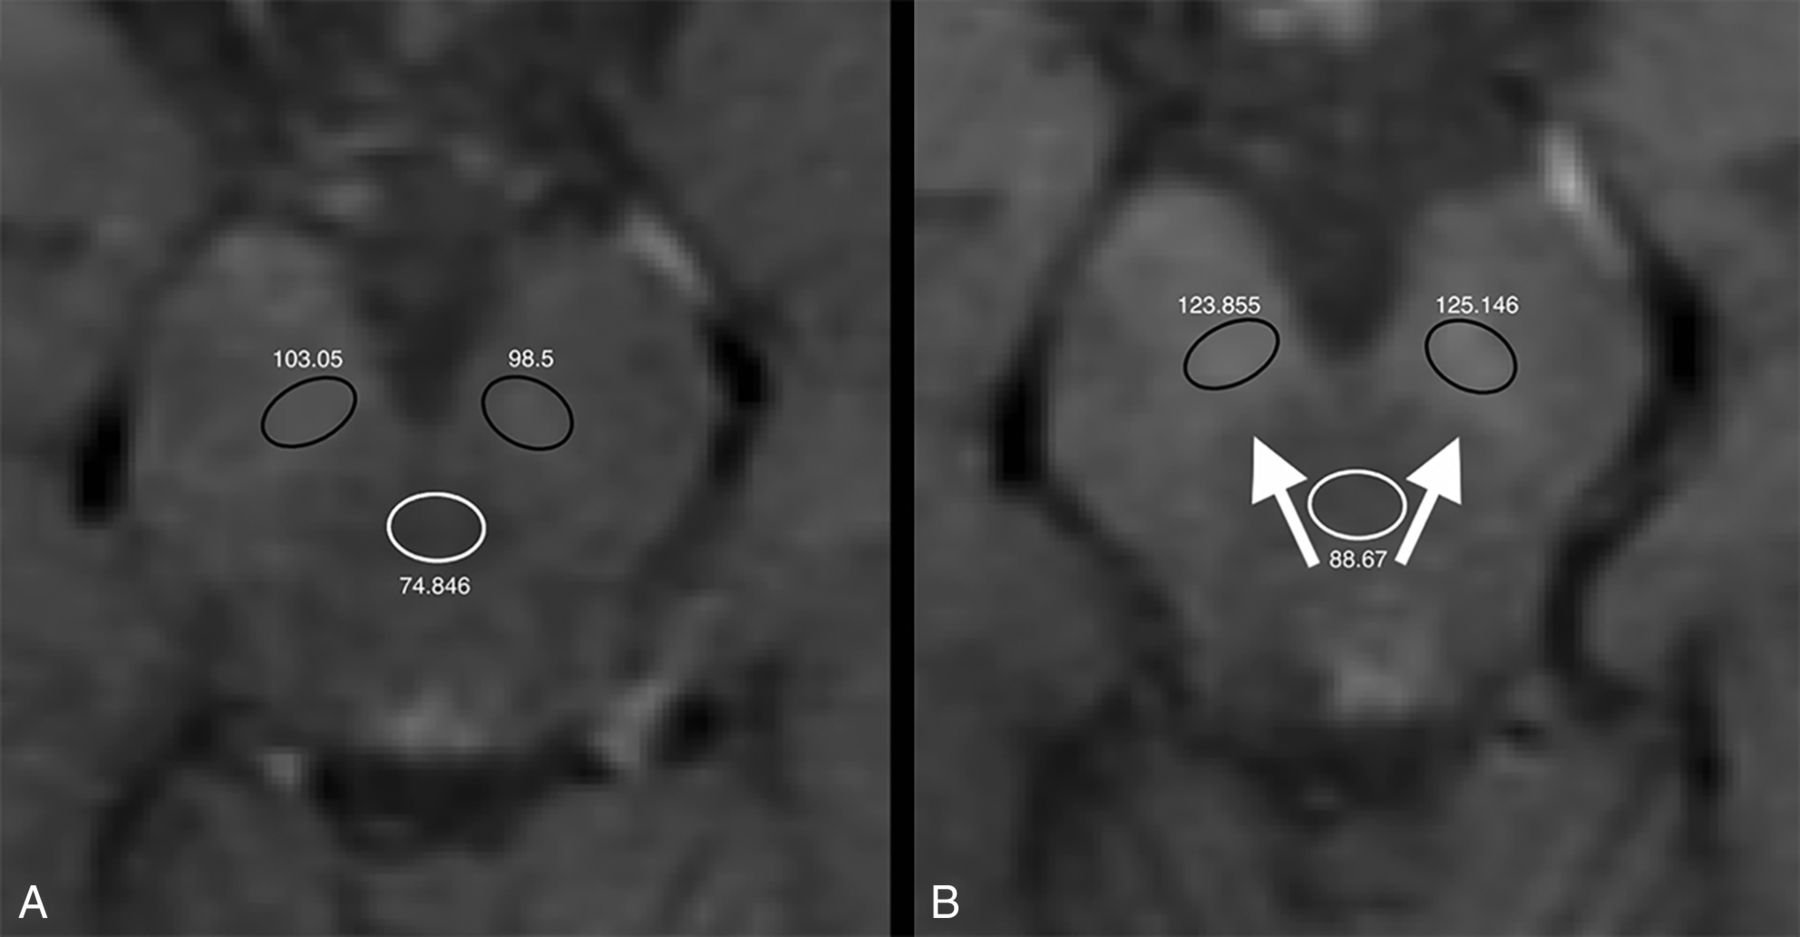

Unenhanced axial T1-weighted images at the first (A) and seventh (B) contrast-enhanced MR imaging of a 26-year-old man with relapsing-remitting multiple sclerosis treated with glatiramer acetate. Absolute numbers of signal intensity measurements are reported for each ROI (black circles indicate the substantia nigra ROIs; white circles, the midbrain ROIs). Increased signal intensity in the substantia nigra at the last MR imaging scan is shown (white arrows). TR = 500 ms; TE = 9 ms; section thickness = 3 mm; matrix =192 × 256.

The GP-to-thalamus, SN-to-midbrain, and DN-to-CP SI ratio differences between the first and last MR imaging scans in our population were significantly higher than 0 (P < .001, P < .001, and P = .002, respectively), with mean values of +0.0251 ± 0.0432 (95% CI, 0.0165–0.0336), +0.0262 ± 0.0673 (95% CI, 0.0128–0.0395), and +0.0266 ± 0.0841 (95% CI, 0.0099–0.0432), respectively (Fig 2 and On-line Figs 1–3).

In patients who had ≥6 L-GBCA injections, the difference in SI ratios between the first and last MR imaging scans was statistically significant for the GP (P < .001), SN (P < .001), and DN (P = .001), but it was not significant in patients with ≤5 injections (P = .059, P = .572, and P = .821, respectively) (Fig 3). These differences were also significantly higher in patients who had ≥6 injections compared with patients with ≤5 injections (P < .001, P < .001, and P < .001, respectively).